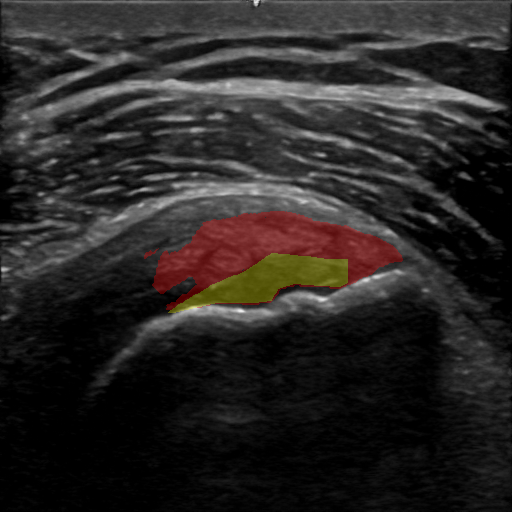

We used the AdamW [31] optimizer, with learning rate of 4e34superscript𝑒34e^{-3}4 italic_e start_POSTSUPERSCRIPT - 3 end_POSTSUPERSCRIPT, and standard betas to optimize the positive points pts¯possuperscript¯𝑝𝑡𝑠𝑝𝑜𝑠\bar{pts}^{pos}over¯ start_ARG italic_p italic_t italic_s end_ARG start_POSTSUPERSCRIPT italic_p italic_o italic_s end_POSTSUPERSCRIPT. The optimized positive tendon points selected by this model serve as k𝑘kitalic_k negative prompt points, ptsnegpts¯pos𝑝𝑡superscript𝑠𝑛𝑒𝑔superscript¯𝑝𝑡𝑠𝑝𝑜𝑠pts^{neg}\leftarrow\bar{pts}^{pos}italic_p italic_t italic_s start_POSTSUPERSCRIPT italic_n italic_e italic_g end_POSTSUPERSCRIPT ← over¯ start_ARG italic_p italic_t italic_s end_ARG start_POSTSUPERSCRIPT italic_p italic_o italic_s end_POSTSUPERSCRIPT, towards the foreground pathology segmentation. This process is illustrated in Fig. 3.

Refer to caption

Figure 3: An illustration of our negative (background) points selection module. In addition to the positive selected points (Sec. 3.1), negative points are selected randomly from the modified ground-truth tendon mask. The points are flipped to initialize the settings of the complementary tendon segmentation problem. Our points optimization model optimizes prompt points selection w.r.t. the complementary tendon zero-shot segmentation problem (Sec. 3.2). Finally, prompt points are again flipped to account for positive and negative prompt points towards the pathology segmentation.